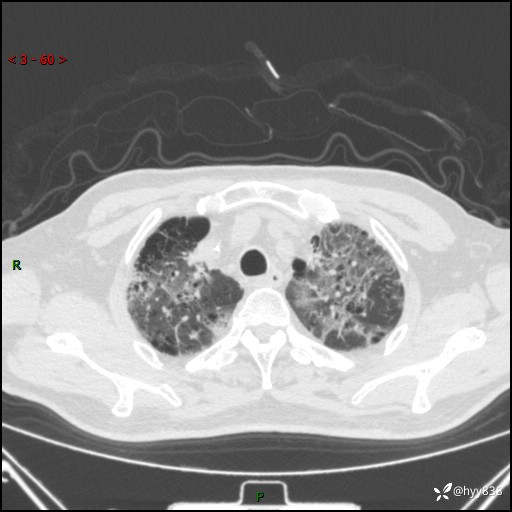

患者性别:男

患者年龄:64岁

简要病史:肝内胆管癌综合治疗后2周余,咳嗽、发热,咳白色泡沫痰。

辅助检查:CT

临床诊断:感染?

讨论:病变性质?